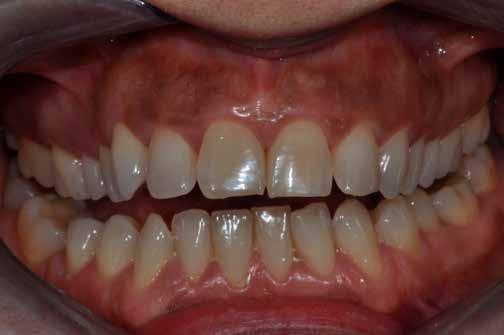

Egy 30 éves, negatív kórtörténettel rendelkező beteg azzal a kéréssel fordult hozzánk, hogy cseréljük ki az UR1 traumája után, 10 évvel korábban készült korábbi kompozit-helyreállítást.

A klinikai vizsgálat során az UR1 reagál a viabilitási tesztre, és az ugyanazon a napon készült röntgenfelvételen nem mutat periapikális elváltozásokat (1. ábra).

Az UR1 elszíneződött, és palatálisabb helyzetben van, mint az ellenoldali központi UL1 (2. ábra)

Az esztétikai elemzés a gingivális zenit aszimmetriáját mutatja az UR1 és az UL1 között. Parodontális szonda segítségével, plexusérzéstelenítés után, az IA

típusú funkcionális hám megváltozott passzív erupcióját igazoljuk Coslet és mtsai. osztályozása szerint (3. ábra)

A lehető legkonzervatívabb helyreállító kezelés elvégzése érdekében a páciensnél, figyelembe véve a megtartott fogelem korát és vitalitását, a tervezés és a diagnosztikai felviaszolás után a közvetlen kompozit-helyreállítás elvégzése mellett döntünk.

1. ábra: Röntgenfelvétel periapikális elváltozás nélkül. – 2. ábra: Az UR1 elszíneződése és palatális helyzete.

3. ábra: Az esztétikai elemzés a gingivális zenit aszimmetriáját mutatja. – 4. ábra: Az UR1 izolálása kofferdámmal.